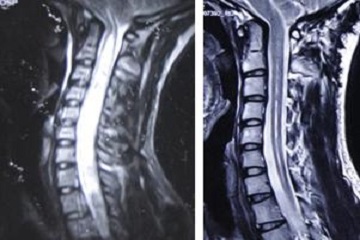

脊髓空洞癥患者,多表現(xiàn)為進(jìn)行性加重的神經(jīng)功能障礙。在初期肩背部及上肢麻木、疼痛、痛溫覺(jué)消失,沒(méi)有引起足夠重視或診斷不清的情況下,患者可以出現(xiàn)進(jìn)行性加重。

脊髓空洞癥的臨床表現(xiàn)有三方面,癥狀的程度與空洞發(fā)展早晚有很大關(guān)系。一般病程進(jìn)展較緩慢,早期出現(xiàn)的癥狀多呈節(jié)段性分布,先影響上肢。

當(dāng)空洞進(jìn)一步擴(kuò)大時(shí),髓內(nèi)的灰質(zhì)和其外的白質(zhì)傳導(dǎo)束也被累及,于空洞腔以下出現(xiàn)傳導(dǎo)束功能障礙。因此,早期病人的癥狀比較局限和輕微,晚期癥狀則表現(xiàn)廣泛甚至出現(xiàn)截癱。